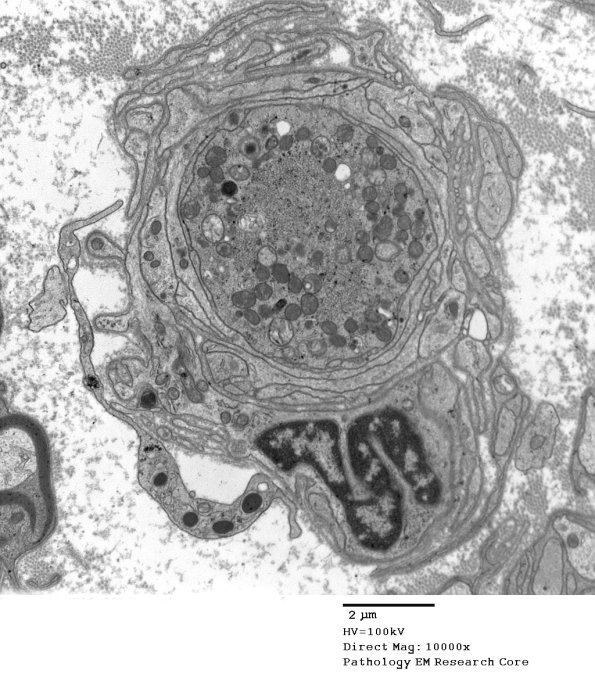

11M1,2 In this axon there are collections of subcellular organelles, tubulovesicular elements (between arrowheads, 11M2) and autophagosomes. (electron micrographs)